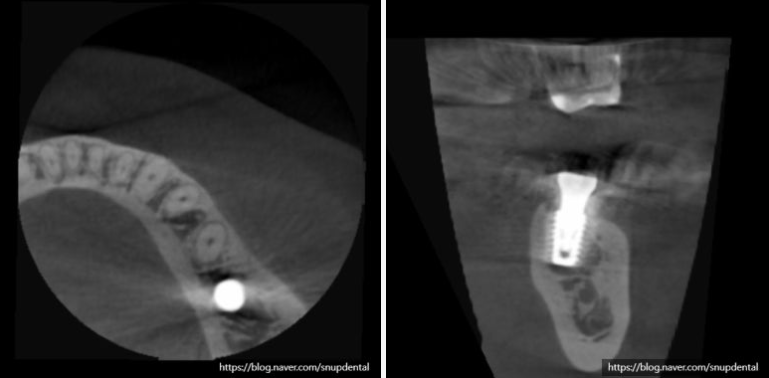

부분 CT 상에서 현재 뼈 상태 및 임플란트 식립 계획을 세워봅니다.

임플란트 수술 후 구강 내 사진 및 부분 CT 캡처 사진입니다